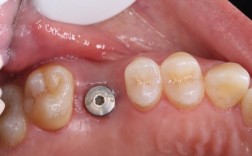

| 种植手术 | 局部麻醉后,在牙槽骨植入种植体,微创技术(如即刻种植)可缩短手术时间,缝合伤口 | 30-90分钟 | 术后24小时内避免刷牙、漱口,遵医嘱服用抗生素 |

| 戴牙冠 | 种植体骨结合(3-6个月后),通过3D口扫制作牙冠,安装并调整咬合关系 | 1-2周 | 初期避免用种植牙咬过硬食物(如坚果、骨头),适应后可正常咀嚼 |